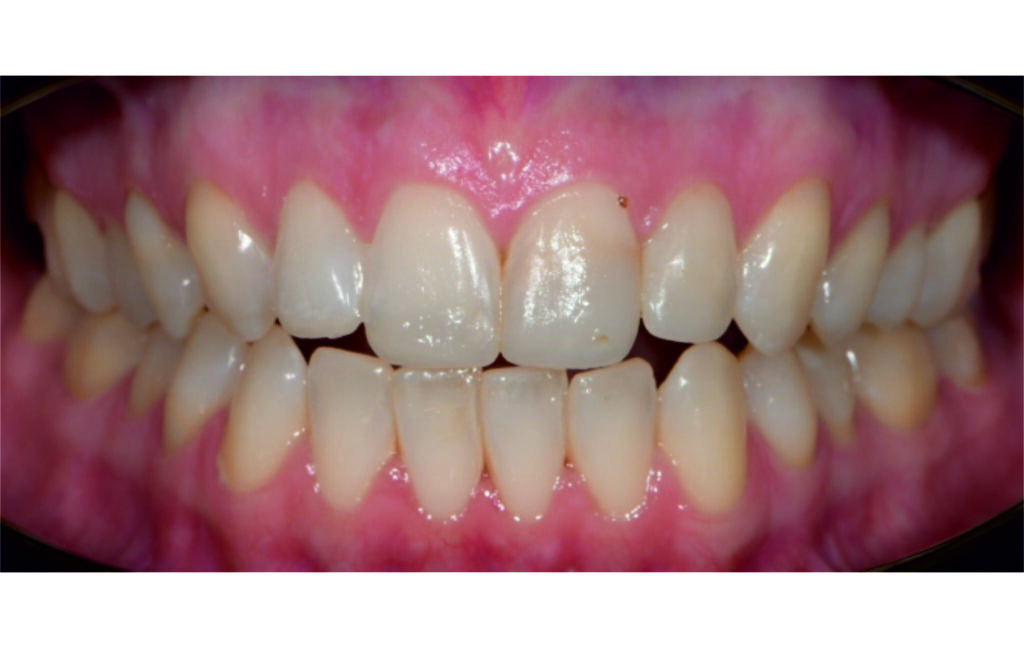

Angle Class II 2mm on the right, Angle Class II 2mm on the left, light mandibular asymmetry to the right, lower central line 1mm to the right, upper central line 1,5mm to the left, 1mm overjet and overbite. Sagittal asymmetry of upper dental arch. Light crowding upper and lower frontal segments, severe attrition of posterior teeth, night bruxism. Normal sagittal position of both jaws, high angle case, steep mandibular ramus,excessive lower facial height, open bite tendency.

The case initially presented as a moderate Class II on the right and a Class II tendency on the left, with tapered dental arches and an anterior open bite extending to tooth 26 in segment II.

In segment I, the open bite reached up to the first premolar.

A 1.5 mm deviation of the upper dental midline to the patient’s left was noted, along with a slight mandibular midline shift to the right, likely due to asymmetrical mandibular growth observed in the facial structure. Severe mesial rotations of teeth 16 and 26 were evident in the initial records. As derotation of 16, 26, 17, and 27 progressed up to aligner 16, the premolars in segments I and II moved distally, resulting in a bilateral Class I relationship, as intended in the initial treatment plan.